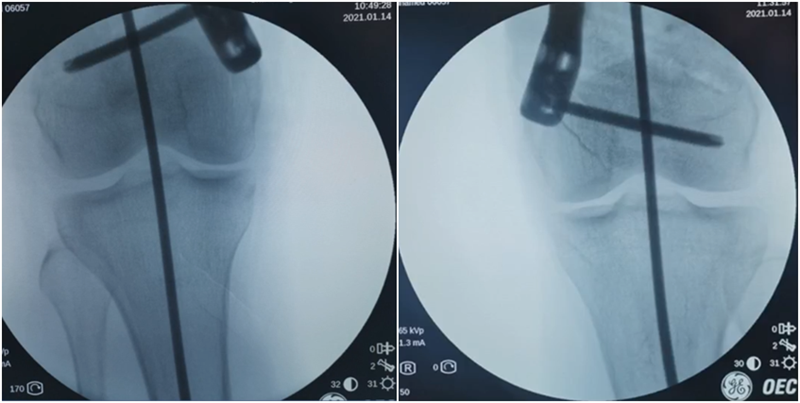

术中发现螺钉松动,截骨端出现坎插迹象。

近端螺钉松开,调整力线,重新固定后,在外侧加小钢板抗旋。

术后10周复查,力线较好。